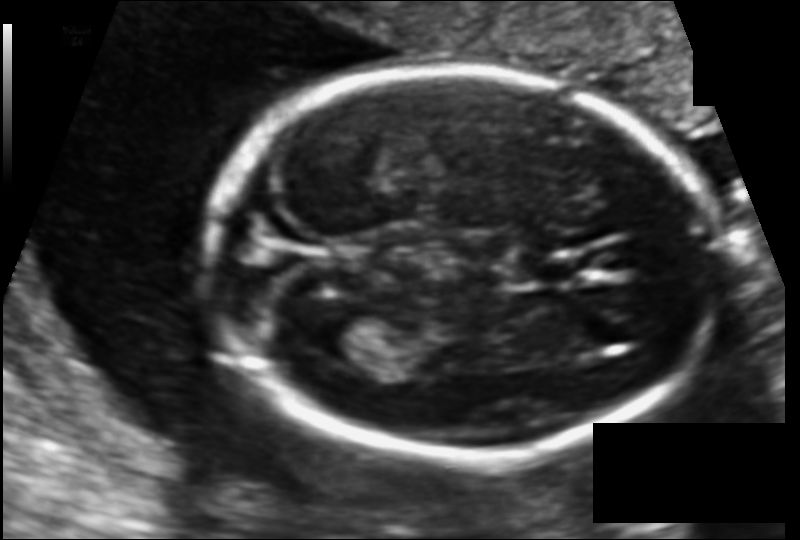

来看下此次任务中,待增强的图像和标签,主要是为了做图像分割做图像准备。这个图像懂的应该能看出来,这是一个婴儿头围的医学图像,现实场景意义很强。上图(以3张图为例):